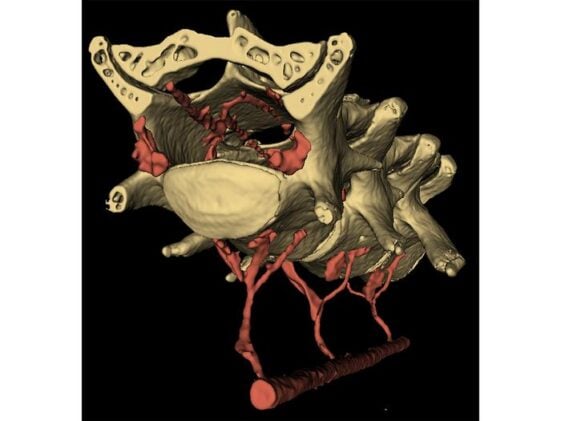

“In this study, we found that when the abdominal muscles contract, they push blood from the abdomen into the spinal cord, just like in a hydraulic system, applying pressure to the brain and making it move,” Drew said. The plumbing that makes this possible is a structure called the vertebral venous plexus, a network of valveless veins running between the abdominal cavity and the spinal canal. The VVP (as anatomists call it) is known in humans, where it’s thought to help buffer intracranial pressure during postural changes. Whether mice even had one was unclear until the team filled the vascular systems of two mice with a radiopaque compound and examined them with micro-CT imaging. The scans showed the plexus clearly, with small holes in the lumbar vertebrae through which veins thread between the abdominal cavity and the interior of the spinal column. When the abdominal muscles squeeze, they compress blood into this network. The blood moves into the spinal canal, narrows the dural sac surrounding the spinal cord, and drives cerebrospinal fluid cranially, pushing the brain forward and outward within the skull.